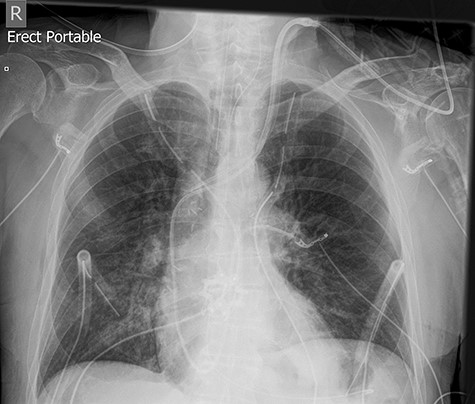

The left basal chest drain was removed without incident on Day 5. However, the nurse encountered resistance during attempted removal of the right basal chest drain. The intern was subsequently notified. Resistance was also encountered by the intern during a further attempt to remove the chest drain. A chest X-ray performed earlier in the day was reviewed (Fig. 2). It demonstrated kinking of the drain around a rib. The intern altered the direction of traction in order to account for the kinking but, during gentle traction, the chest drain fractured at the 14-cm mark (Fig. 3) and became retained within the right hemithorax (Fig. 4). The thoracostomy wound was closed and senior help was immediately sought.

Chest X-ray demonstrating kinking of the chest tube around a rib on the right side.